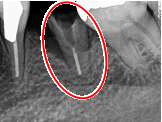

レントゲンで詳しく診てみると、虫歯が歯根のほうまで進行し、保存することができないことがわかり、抜歯しました。抜歯後、骨が大きく欠損していましたので、骨造成を行いインプラントを2本埋入しました。

Before

【抜歯後】